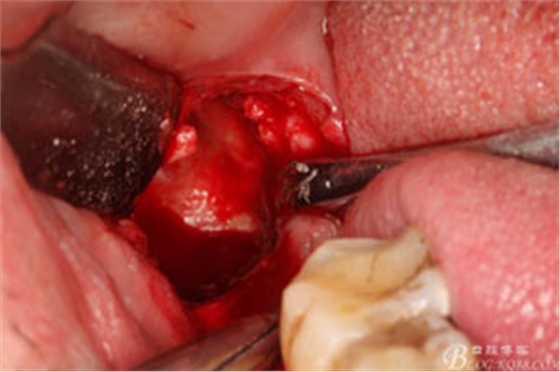

圖12. 先取出48牙冠

圖13.從頰側(cè)和舌側(cè)兩個(gè)方向用挺。挺出牙根